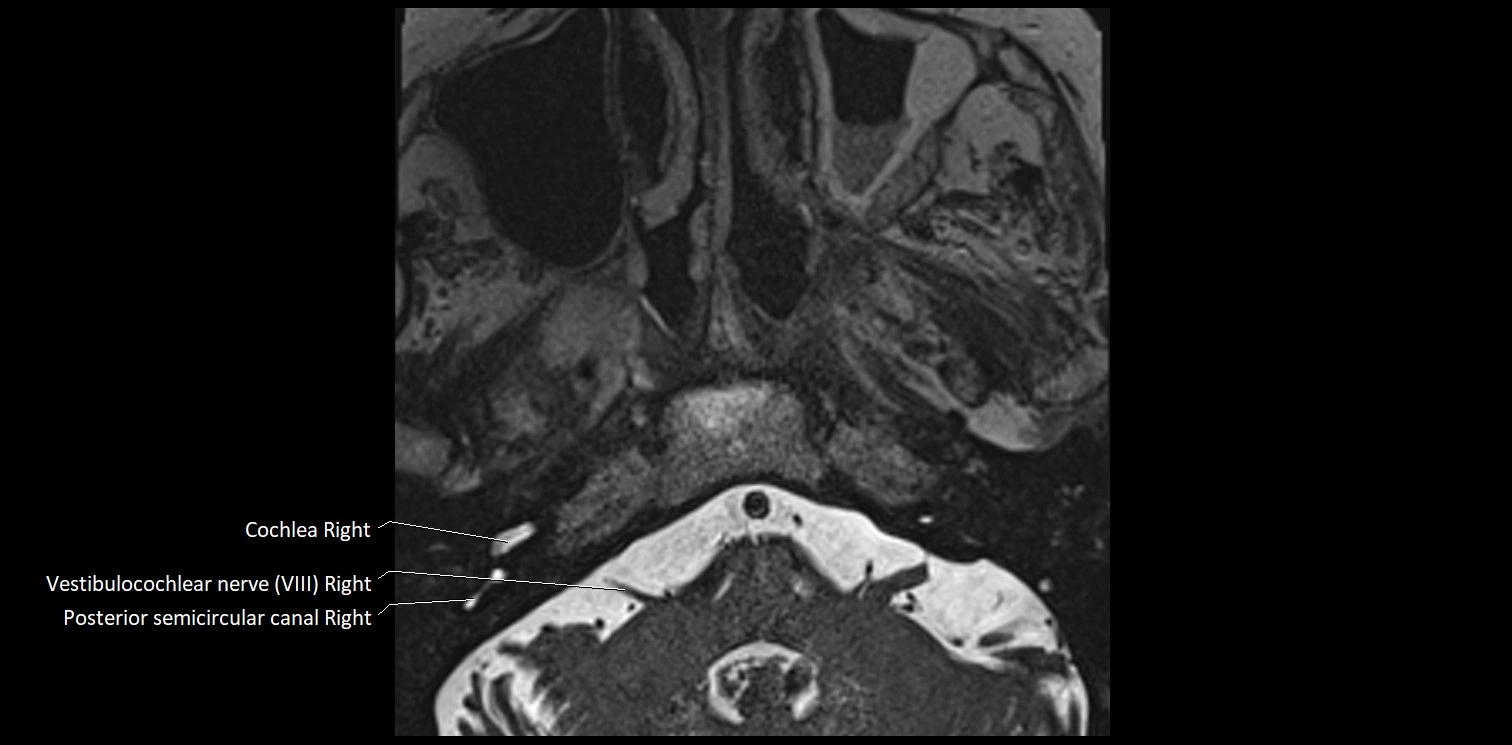

MRI images

image